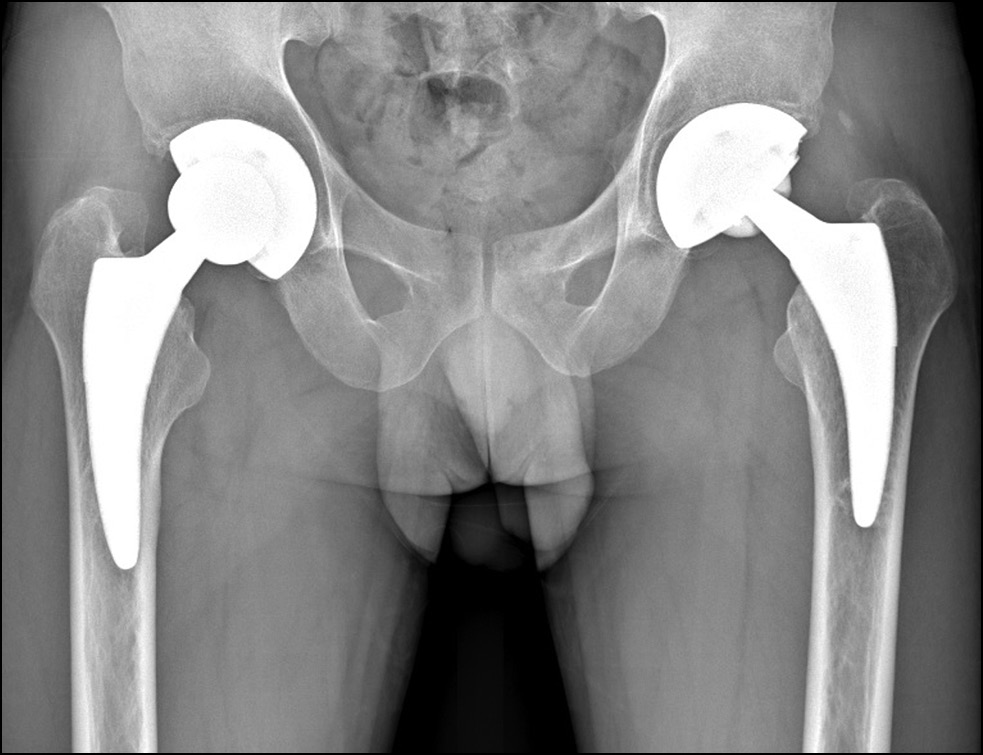

При современном обеспечении ЗФТ использование бесцементных имплантатов показало большую долговечность в сравнении с цементной фиксацией. Это объясняется тем, что при БГ сохраняется репаративный потенциал костной ткани, что обеспечивает остеоинтеграцию и вторичную биологическую фиксацию бесцементных эндопротезов [16]. При колбовидном расширении проксимального отдела диафиза бедра мы отмечали проксимальную фиксацию компонентов в межвертельной зоне (рис. 6). Хорошие результаты применения укороченных бедренных компонентов также подтверждают это (рис. 7).

Рис. 7. Укороченные бедренные компоненты Fitmore через 4 года после операции.

Fig. 7. Short Fitmore femoral stems four years post-surgery.